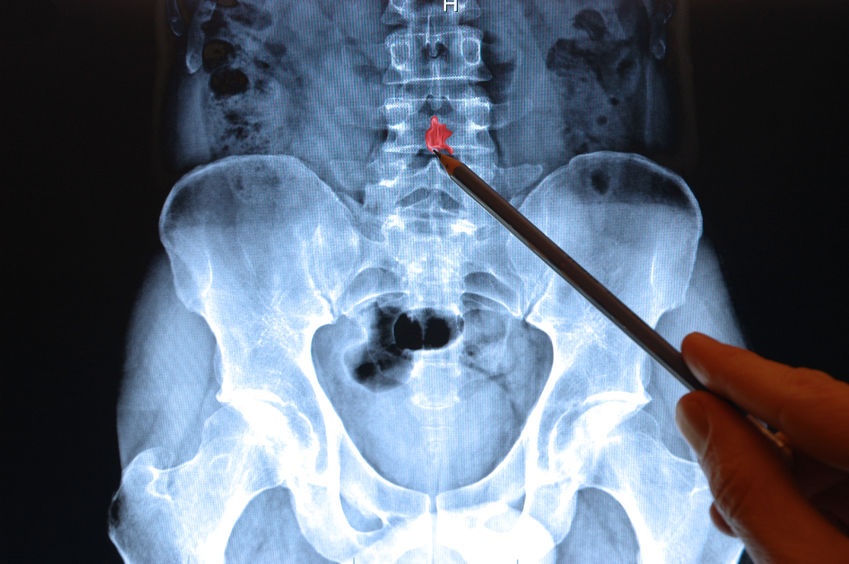

Spinal stenosis is characterized by a narrowing of the spinal canal. The condition causes pain, tingling and muscle weakness.

Lumbar spinal stenosis is the more common type of stenosis. Characterized by the narrowing of the lower end of the spine, if you suffer from this condition you probably experience pain while walking standing or walking.

A second type of stenosis is known as cervical spinal stenosis. This is caused by the narrowing of the spine closer to the neck and can be made worse by looking up or lifting objects over the head.

The size of the spine is genetically determined but can be at risk of narrowing because of arthritis, disc narrowing or spurring, spinal misalignment, disc herniations, and simple gravity. Aging also has an impact on spinal stenosis.

Spinal decompression is a non-surgical method used to relieve spinal stenosis by gently stretching the spine. The technique is performed on a specialized table by certified doctors or chiropractors. Studies show that close to 90% of patients benefit from the DRX9000 spinal decompression treatment.